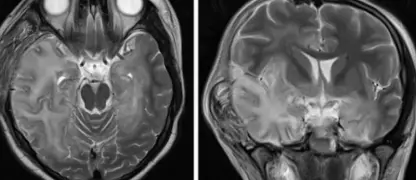

Rabies is a deadly viral infection transmitted through bites or scratches of infected animals. It attacks the nervous system, causing severe neurological symptoms and, if untreated, is almost always fatal.

Rabies affects human nervous system severely